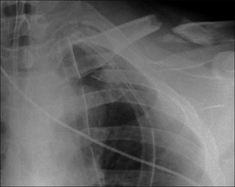

Figure 32.15 Male. Age 23. RTA. Left-sided rib fractures (note that a flail segment is present). Pneumothorax. The consolidation in the left upper lobe is an area of lung contusion.